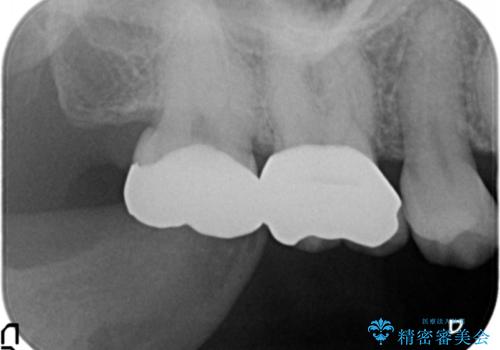

- 笑ったときに目立つ奥歯の銀歯を白くしたいという希望で来院されました。

銀歯を除去し、ジルコニアクラウンによる審美性の回復を計画します。

- 33万円(仮歯・ジルコニアクラウン×3)費用は治療当時の料金となります